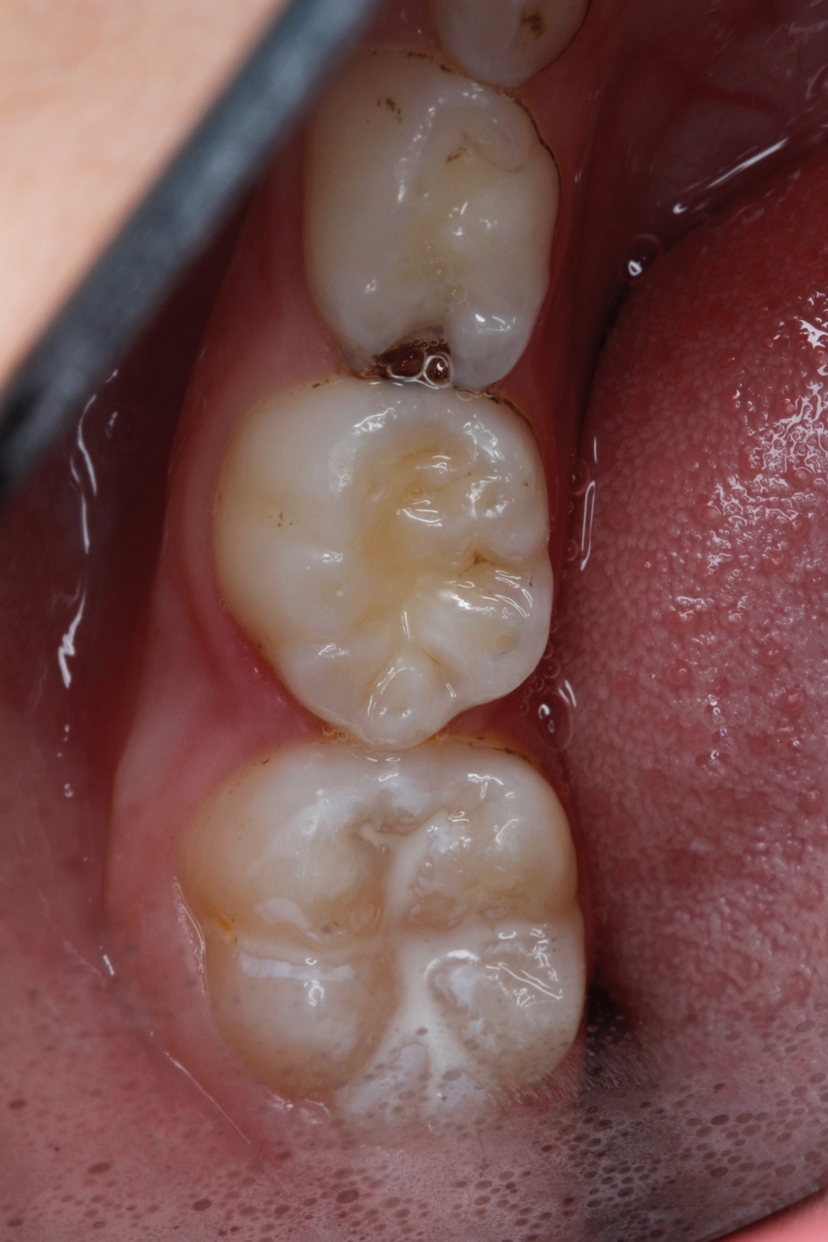

牙齿的咬合面布满了深浅不一的窝沟,这些细小的缝隙最容易藏匿食物残渣和细菌。儿童由于刷牙技巧不够熟练,很难彻底清洁这些部位。窝沟封闭技术就是将一种特殊的树脂材料涂布在牙齿表面,形成一层保护膜,将窝沟封闭起来,阻止细菌和食物残渣的侵入。

这项技术操作简单快捷,整个过程无痛无创。医生会先清洁牙齿表面,然后涂抹封闭剂,最后用特殊的光固化。整个过程只需要几分钟,孩子就能获得持久的保护。

窝沟封闭的最佳时机是在恒磨牙萌出后尽快进行,一般在6-8岁和11-13岁这两个阶段。这时新长出的恒牙还没有受到细菌侵蚀,及时进行封闭能获得最佳效果。